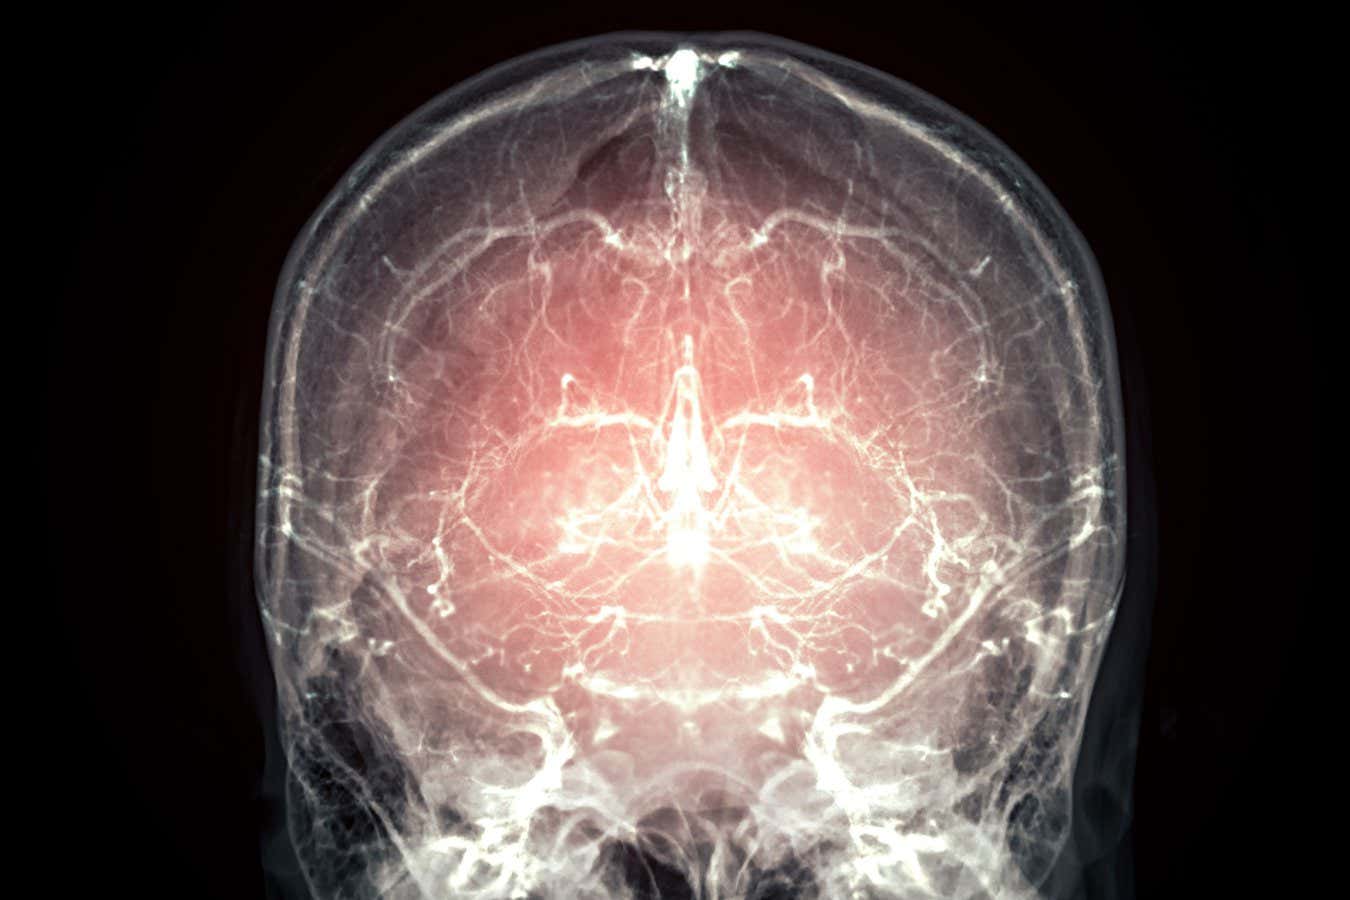

Could our brains one day be preserved in a way that locks in our thoughts, feelings and perceptions?

An entire mammalian brain has been successfully preserved using a technique that will now be offered to people who are terminally ill. The intention is to preserve all the neural information thought necessary to one day reconstruct the mind of the person it once belonged to.

Wróbel says that in theory, they could use this protocol “to reconstruct the three-dimensional structure of the neurons and the connections between them”. This is known as the connectome, and it is hoped that, by mapping it out, it might help us understand how the brain produces our thoughts, feelings and perceptions. So far, scientists have managed to map only a small part of the mouse brain in this way, which took seven years to complete.